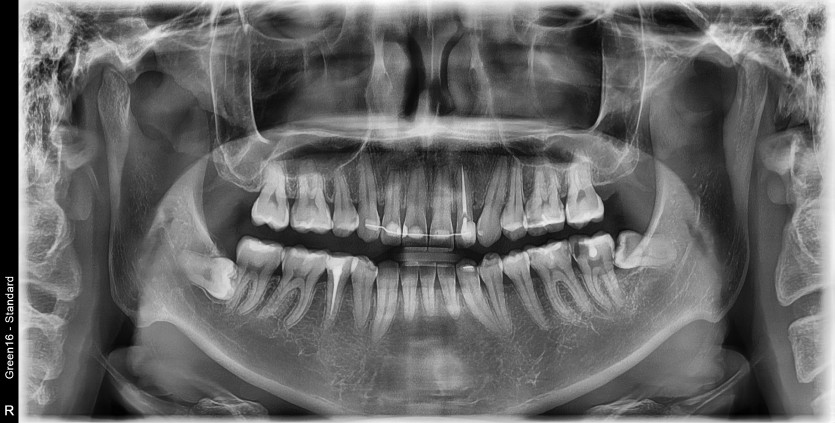

#38 사랑니 발치

구강 외과 전문의가 당일 발치했습니다.